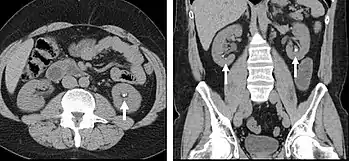

Kidney masses

Detection and characterization of renal parenchymal masses is a frequent indication for CT. An initial noncontrast CT is important for detecting calcium or fat in a lesion, and to provide baseline attenuation of any renal masses. Following noncontrast scanning, intravenous contrast is injected and a corticomedullary phase is obtained at approximately 70 seconds (figure 7a, 7b). The corticomedullary phase is characterized by enhancement of the renal cortex as well as the renal vasculature. This phase is valuable in the evaluation of benign renal variants, lymphadenopathy and vasculature, however certain medullary renal masses may not be visible during this phase due to minimal enhancement of the medulla and collecting system. The parenchymal phase is obtained approximately 100–200 seconds after the injection of contrast material (figure 7c). Parenchymal phase imaging demonstrates continued enhancement of the cortex, enhancement of the medulla, and various levels of contrast material in the collecting system. The parenchymal phase is highly important for the detection and characterization of renal masses, parenchymal abnormalities, and the renal collecting system. This method of imaging does not evaluate for abnormalities of the collecting system.

Common renal masses can occasionally be differentiated from each other using this imaging technique. Renal cell carcinomas and oncocytomas typically demonstrate intense heterogeneous enhancement on the parenchymal phase images and cannot be reliably differentiated from each other but can be distinguished from other renal masses. Angiomyolipomas (AML’s) also demonstrate intense contrast enhancement but characteristically contain macroscopic fat which can be detected on the noncontrast images, and can help to differentiate AML’s from renal cell carcinomas and oncocytomas. Renal lymphoma on the other hand, will often have decreased enhancement when compared to the renal parenchyma on the parenchymal phase images.

FIGURE 7. Selected images from a renal mass specific protocol CT. Corticomedullary phase (axial 7a) demonstrates peripheral enhancement of the renal cortex with minimal opacification of the renal medulla. There is a large renal cell carcinoma in the left kidney (right in image) which can be differentiated from the normal renal parenchyma by the heterogeneous and differential enhancement. The renal artery and vein are opacified in this phase as well. The collecting system is not opacified (coronal reformat 7b). In the parenchymal phase, the renal cortex and the medulla are enhancing. The renal cell carcinoma in the left kidney is not as well defined when compared to the corticomedullary phase images, but is actually slightly more conspicuous. There is some contrast noted within the collecting system during this phase (7c).